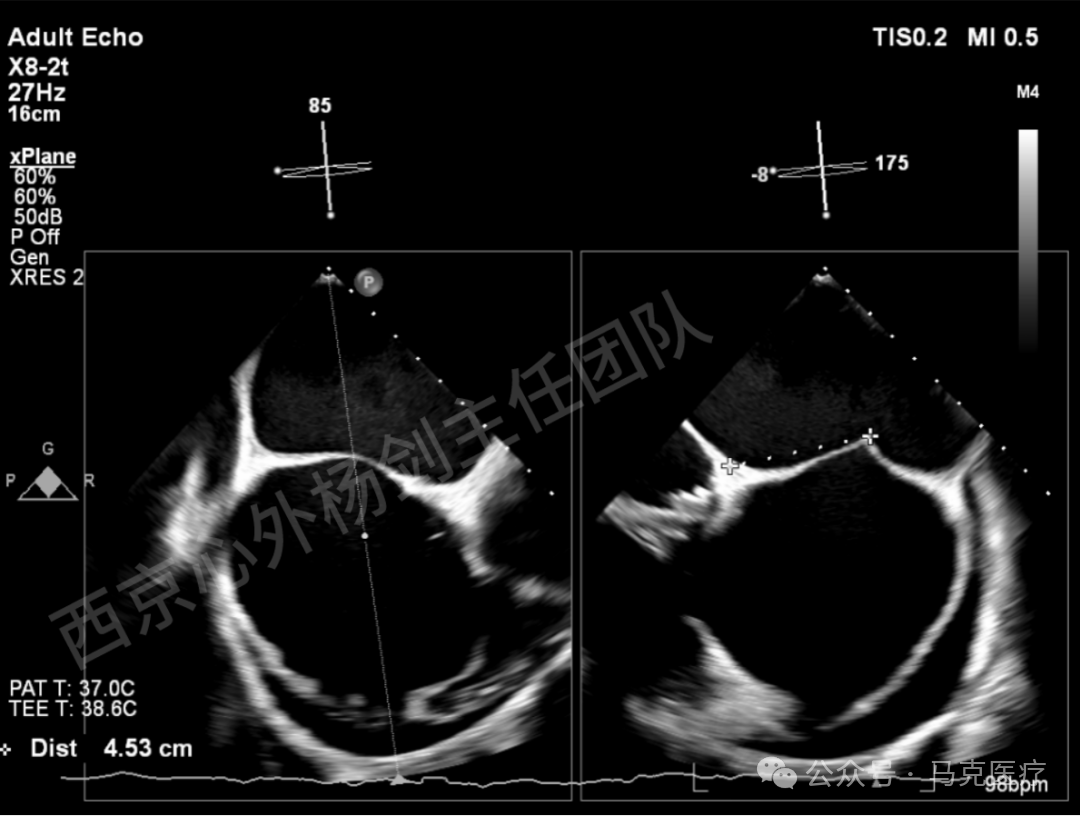

图片

房间隔穿刺,最终高度4.5cm